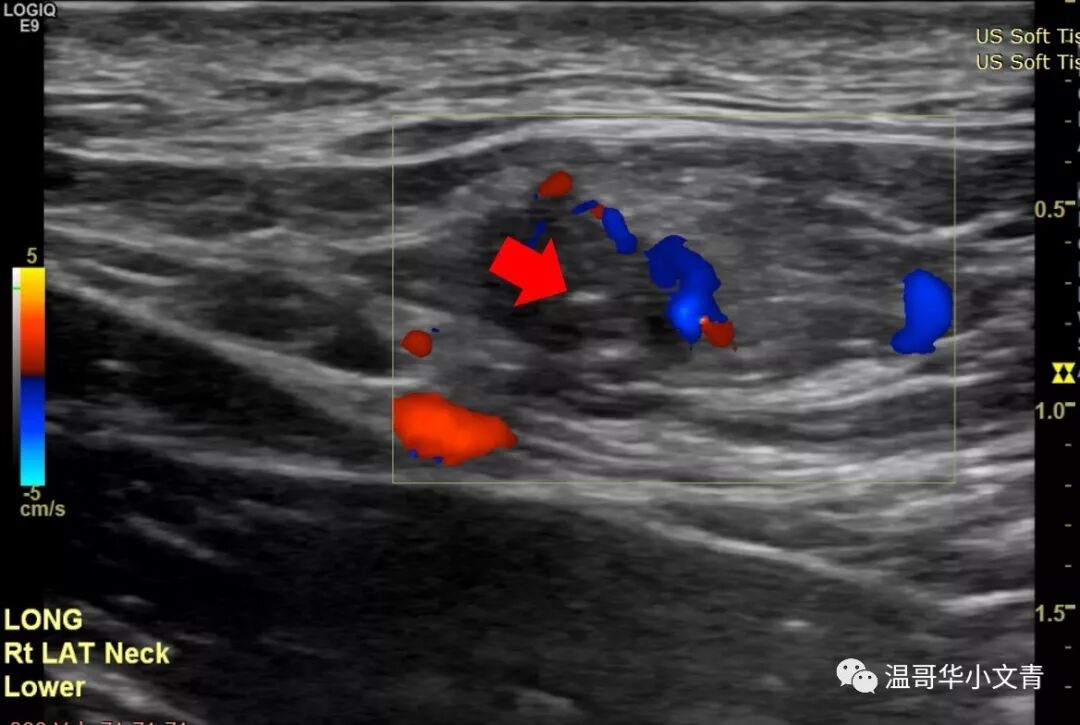

随着知识的普及,大家都知道颈部彩超检查对于甲癌病人非常重要,尤其是乳头状癌和髓样癌的病人。 经常有病友来群里吐槽: “他奶奶的,排队排了两个小时,彩超医生把探头在我脖子上晃了40秒就搞完了,真尼玛瞎搞!” “做了几个医生的彩超,各个结果都不同,真蛋疼!” 所以今天小编就和大家来讨论下彩超检查: 如何正确的进行彩超检查? 如何解读彩超结果? 彩超检查的结果有什么意义? 如何正确的进行颈部彩超检查? 这部分内容取自斯坦福医院的Lisa Orloff,她本身是头颈外科医生,也是彩超师。 术前彩超和术后彩超的操作方式是类似的。不过,术前彩超是越精确越好,术后有时候对彩超的要求反倒不需要那么高,今天主要讨论的是术前彩超。做彩超最重要的是动图,通过动图发现可疑的病灶,再逐个详细分析。Lisa推荐的检查顺序是: A 甲状腺和气管旁中央区淋巴结 (两侧) B 峡部气管前中央区淋巴结 C 喉前中央区淋巴结和声带 D 侧颈大血管周围二三四区淋巴结 (两侧) E 侧颈五区淋巴结(两侧) F 一区淋巴结以及唾液腺 当动图发现了问题之后,再把有问题的地方详细的记录下来,形成一整套图片。最后彩超医生把图片和报告交给内分泌医生或者手术医生,由他们定夺治疗方案。彩超最重要的其实是动图和图片,而不是报告上简单的几行字。 彩超结果能解读出哪些信息? 第一个是判断甲状腺结节的大小,数目和属性。如果甲状腺的结节出现微钙化,纵横比大于一,边界不清晰这些字眼,结节是恶性的可能性就比较高。一般来说拿到图片良恶性都能有个大致判断,有的时候不好判断也没关系,反正还有穿刺。 第二个是如果是甲状腺癌,判断原发肿瘤有没有侵犯周围的组织。比如说这个肿瘤是不是和气管的关系比较密切?是不是有可能侵犯了前被膜?是不是有可能侵犯了后被膜导致和喉返神经关系密切。 第三个是判断淋巴结的转移情况。大家都知道如果淋巴结出现钙化,囊性化,局部高回声基本都是转移的;如果没有淋巴结门结构,形状是圆形那么就是相对可疑的。读图比看文字描述更可靠!因为你会知道这个淋巴结到底有多可疑!或者到底有多坏! 实际上彩超在侧颈淋巴结的区域更为敏感,下面就是一些例子: 右侧颈5区的淋巴结,8毫米,不规则血流。红箭头指向的地方是微钙化,你看图就知道这是乳头状癌的转移淋巴结。 左侧颈4区的淋巴结,6毫米,不规则血流。高度怀疑是转移的淋巴结。 左侧颈3区的淋巴结,7毫米。红箭头指向的地方是钙化点,你知道这是一个乳头状癌转移淋巴结。 左侧颈2区的淋巴结,1.5厘米,没有明显的淋巴结门结构,是一个中度可疑的淋巴结。 当彩超医生阅读完所有的图片之后,就会把信息聚集起来,形成一幅肿瘤分布图,告诉内分泌或者外科医生原发肿瘤到底有多少?腺外侵犯有多少?淋巴结转移有多少?它们在哪里? 彩超检查结果有什么意义? 第一,彩超结果可以指导医生是否需要进一步的影像学检查,比如说颈部的增强CT。 大概有20%-25%的病人在彩超上有明显的转移需要颈部增强CT检查。彩超能看出来结节和气管关系密切,但是要想知道侵犯了气管的多大面积就需要增强CT;彩超能看出来常规的中央区侧颈区的淋巴结转移,但是有的病人可以转移到鼻子后面的淋巴结(咽后淋巴结),胸骨后面的淋巴结(纵隔淋巴结),这时候就需要增强CT。 第二,彩超结果可以指导放射科医生穿刺哪些部位。 一般来说,需要一个恶性证据去展开手术;另外可能影响手术方案的淋巴结也需要穿刺。 第三,彩超结果可以指导手术医生手术的方案。 手术是半切还是全切? 中央区清扫是一侧还是两侧? 侧颈区清扫不清扫,清扫多大的范围? 手术涉及不涉及气管,食道这些关键位置? ...... 第四,彩超结果可以告诉病人大概的预后。 很多人拿到彩超结果还没手术就喜欢问需要不需要碘131?有没有远转?这个确实需要一步步的来看,但是彩超的结果也是一个很好的预判。 如果你的彩超检查很详细但没有显示任何转移,你的预后是非常非常好的,你基本不可能发生远处转移,而且术后需要碘治疗的可能性很小;如果你的彩超显示有大面积的淋巴结转移,你术后基本就需要碘治疗,而且可能还需要一个胸部CT评估肺部的状况。